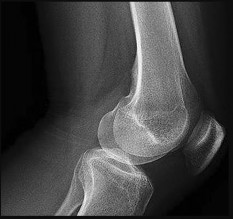

Prepare for the Arab Orthopaedic Board exam with high-yield MCQs, clinical cases, and comprehensive review materials.